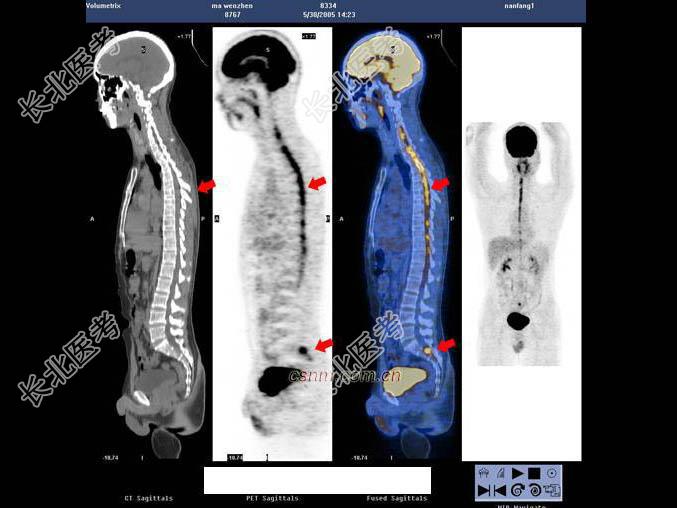

- 多项选择题男,7岁, 2岁时因头痛而就诊,MRI示脑积水、颅内(小脑蚓部及蝶鞍)见多发恶性肿瘤, 临床诊断为髓母细胞瘤。未行手术治疗,多年来一直行放、化疗治疗, 最后一次化疗1个月前结束。因腹胀、恶心、呕吐1周而就诊,CT示: 双侧侧脑室充满肿瘤病灶,PET/CT全身显像如图。正确的表述是 ( )

A、脑干及颈段、胸段、上腰段脊髓内见长条状高代谢病灶,考虑为肿瘤向脑干及大部分脊髓播散、种植转移

B、正常情况下脊髓内无明显放射性浓聚,当出现椎管内肿瘤转移则可表现为18F-FDG明显浓聚,呈“辫子征”

C、肿瘤同时向双侧丘脑及豆状核浸润、侵犯;蝶鞍内块状高代谢病灶,考虑为转移灶

D、肿瘤复发并沿双侧侧脑室弥漫性浸润